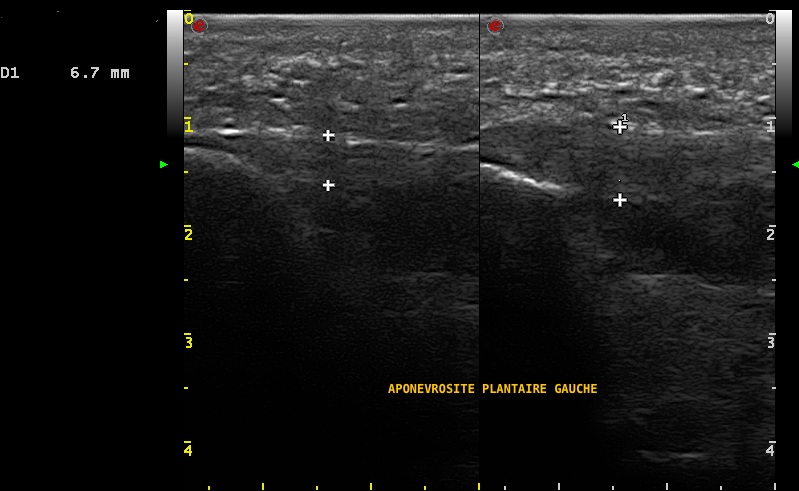

Aponévrosite plantaire gauche symptomatique confirmée par l'échographie